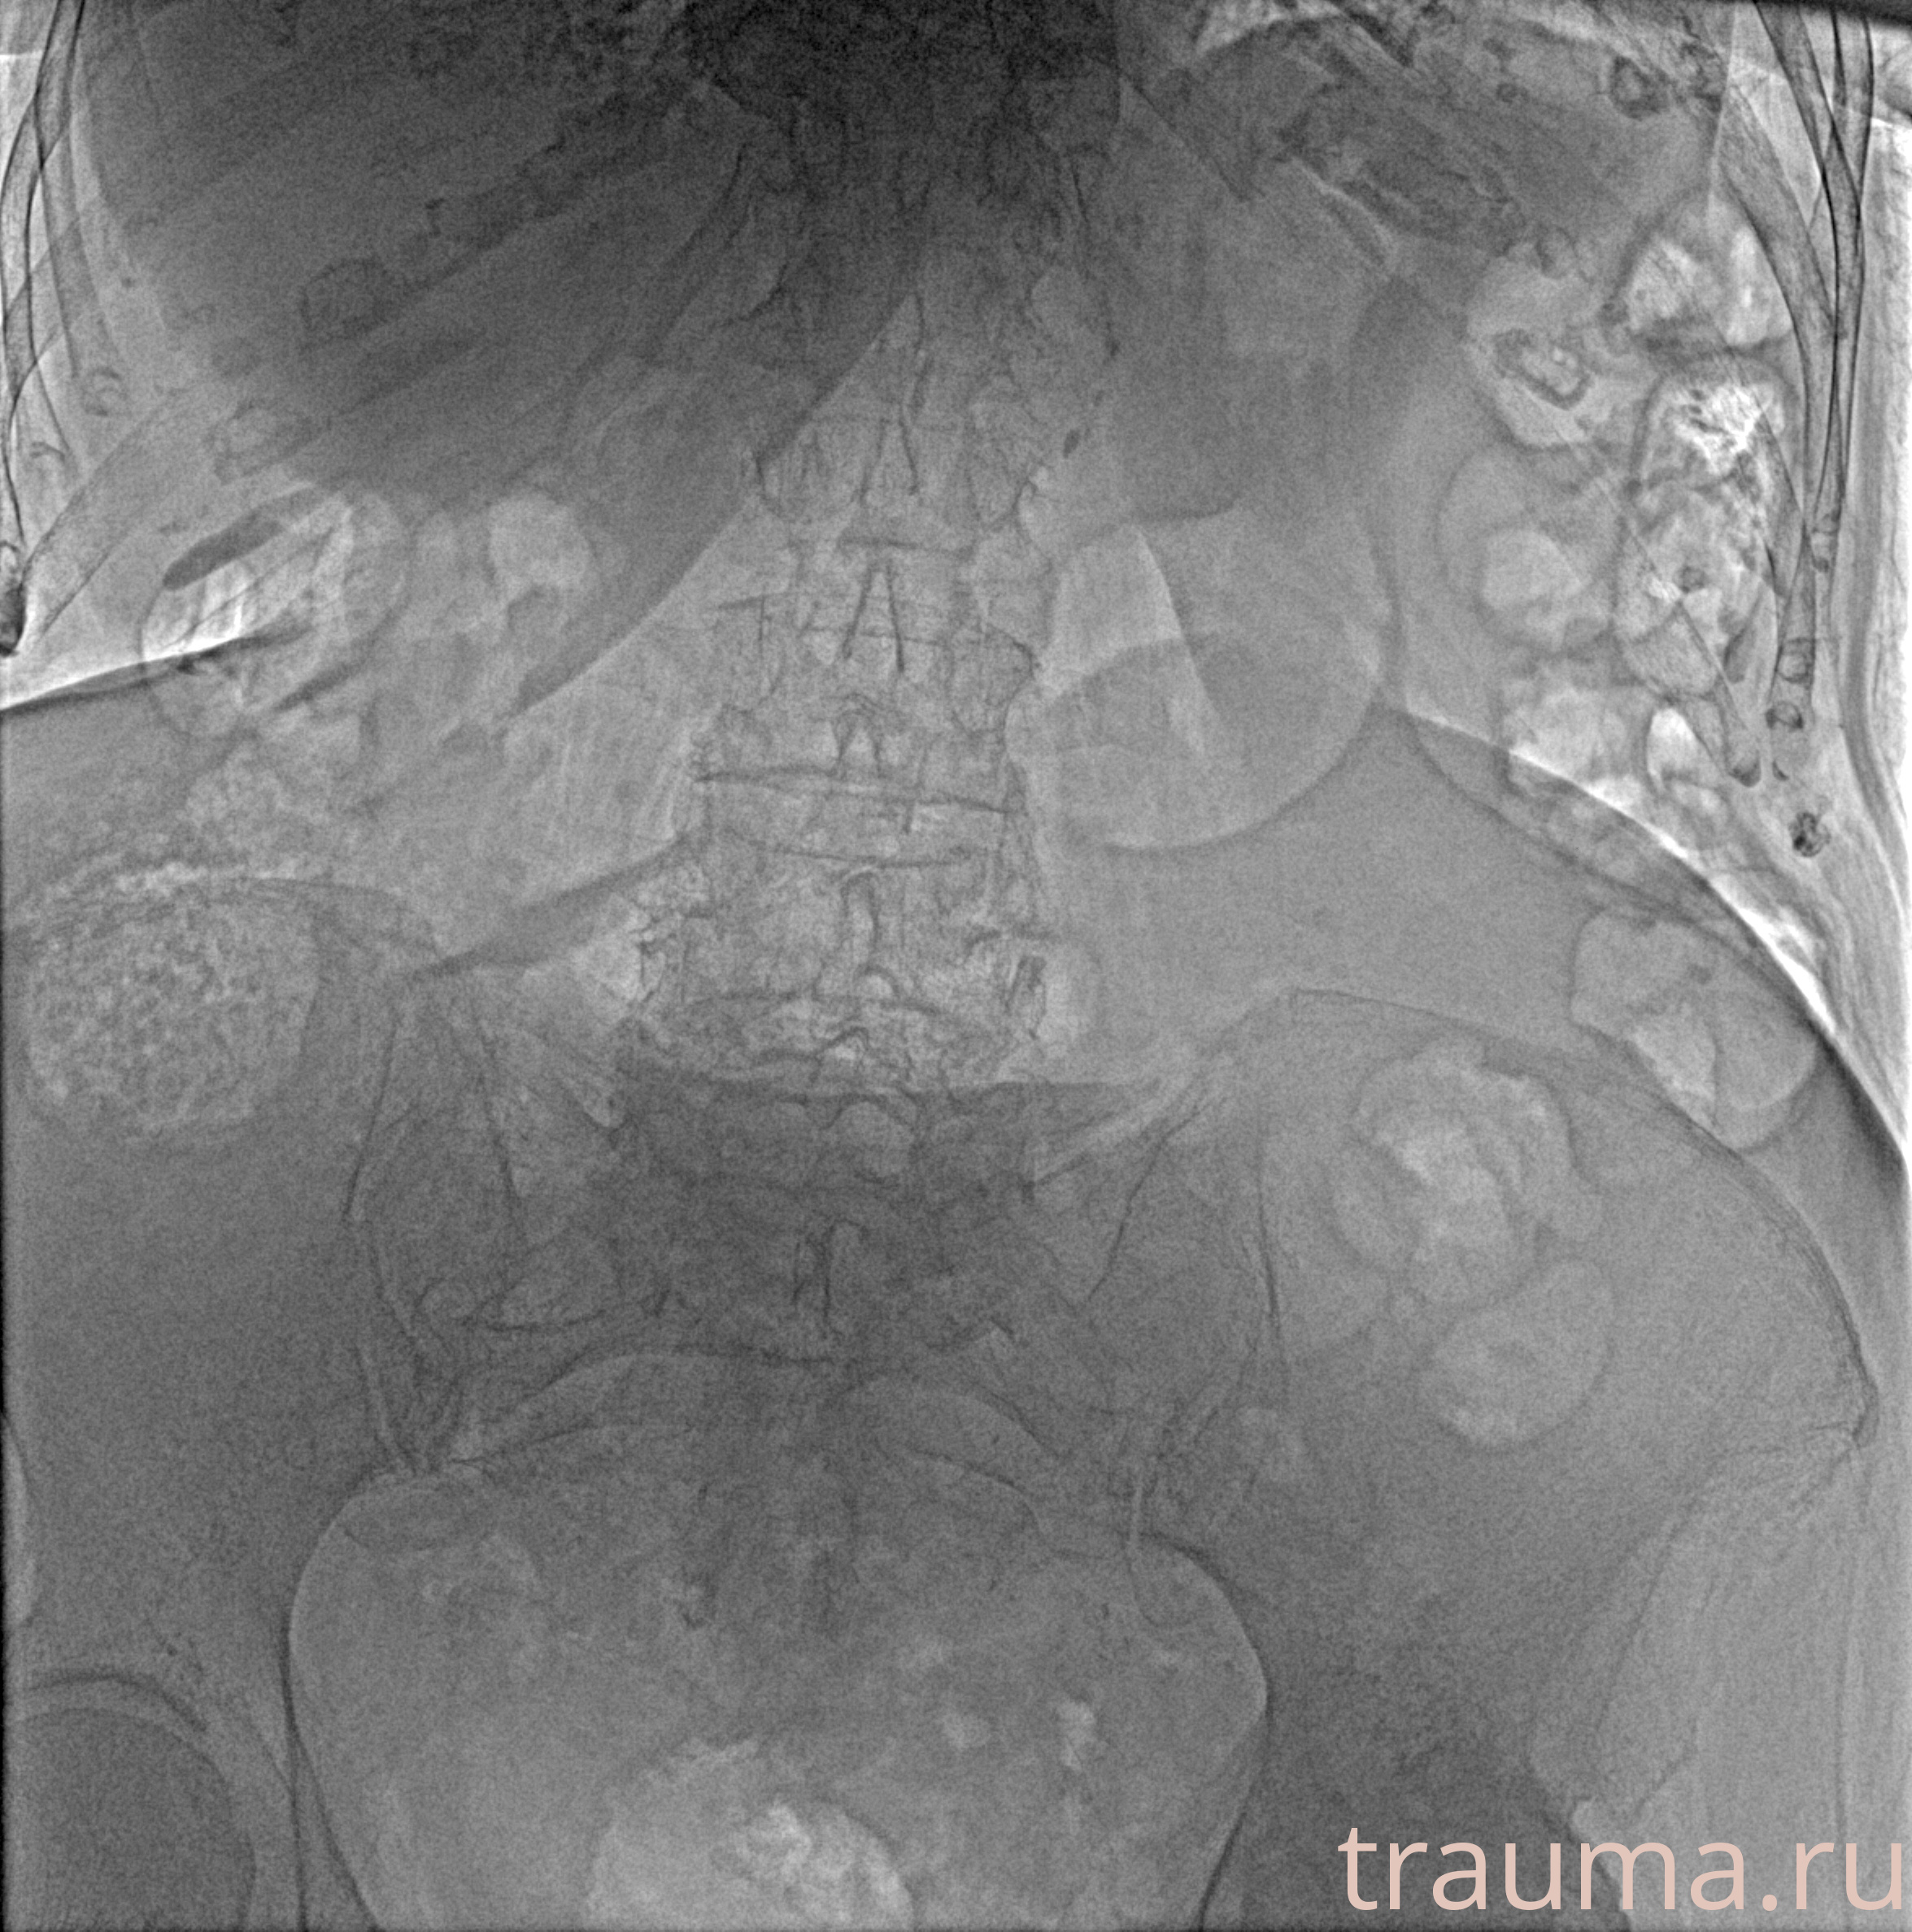

Рентген на дому: по вашему адресу приезжает врач-рентгенолог, травматолог-ортопед с мобильным рентгеновским аппаратом, проводит диагностику травмы или заболевания, делает необходимые рентгенограммы, дает рекомендации по дальнейшему лечению. Получить качественные снимки в домашних условиях возможно благодаря уникальной методике, разработанной МосРентген Центром для института  Склифосовского